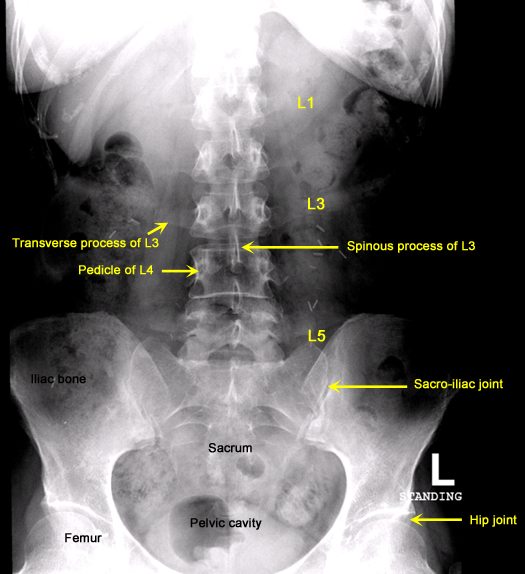

Plain Films of Skull and Spine